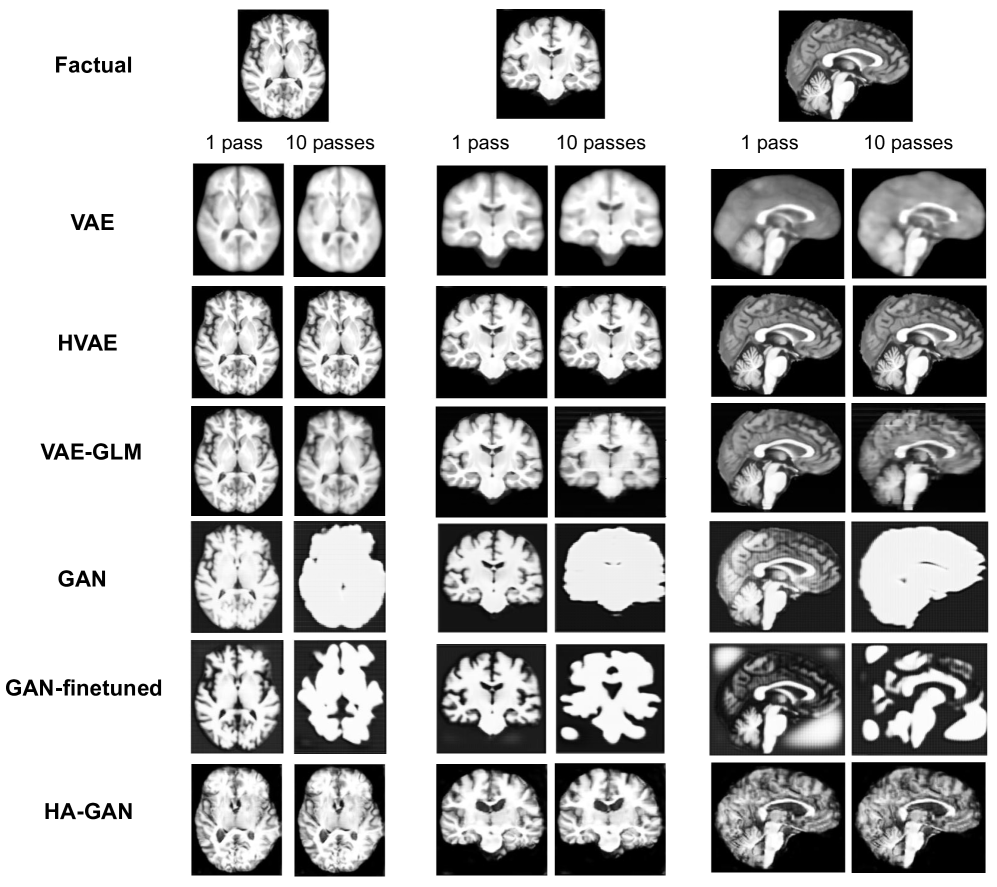

Composition Table 1 demonstrates the exceptional composition performance of HVAE in both distance metrics, maintaining high image fidelity even after 10 passes. VAE-GLM has relatively low l1l_{1} distance and high SSIM after one pass but worsens after ten passes. GAN-based models have the worst composition scores after one pass and further deteriorate after ten passes. Supplementary Fig. 3 confirms these quantitative results of composition. VAE counterfactuals are blurry, losing fine anatomical structures of brain MRIs. This issue comes from the difficulty to reconstruct the high-resolution images directly from latent space. GAN-based models generate unrealistic images and the brightness of brains is prone to change.

Refer to caption

Figure 3: Qualitative evaluation of composition on ADNI dataset. The factual image, counterfactual image after 1, 10 passes are shown for each model.